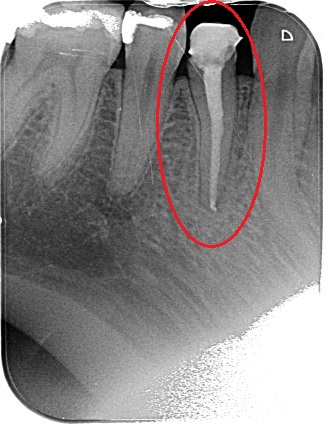

Porovnání průměrného ošetření způsobem plně hrazeným ze zdravotního pojištění (obrázek vlevo) a ošetření způsobem nadstandardním (obrázek téhož zubu po přeléčení vpravo) mohou přinést rentgenologické snímky níže.

Čím přesněji jsou kanálky zaplněny (výsledek práce kontrolujeme rentgenologicky), tím lepší je vyhlídka zubu do budoucna. Známkou selhání ošetření je dlouhodobá přítomnost zánětlivého ložiska okolo zubu v kosti (lidově známé „váčky“), která záporně ovlivňuje stav organizmu a zároveň může kdykoli vést k bolesti a otoku. Naším cílem je tedy vzniku těchto ložisek předcházet.

Při endodontickém ošetření je naším cílem vyčistit kořenový systém zubu (mechanicky i chemicky) a poté jej zaplnit. Kořenový systém sestává z jednoho či více kořenových kanálků, přičemž některé zuby (jmenujme horní první stoličky) mívají běžně tyto kanálky až čtyři. Plnění provádíme čepy složenými z přírodní pryskyřice a oxidu zinečnatého. Takovýto materiál vydrží na místě neomezeně dlouhou dobu, přičemž ale umožňuje práci v nutném případě předělat.